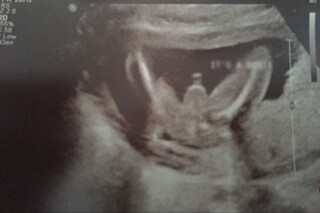

চিকিত্সা পরিষেবায় গাফিলতি। একের পর এক বেসরকারি হাসপাতালের বিরুদ্ধে অভিযোগ উঠেছে। এবার তালিকায় মালদহের নারায়ণপুরের মৌলিক নার্সিংহোম। পুরুষ রোগীকে ইউএসজি রিপোর্টে মহিলা হিসেবে উল্লেখ করে কাঠগড়ায় ওই নার্সিংহোম। বুধবার চাঁচলের বাসিন্দা ছিয়াশি বছরের হাজি মালিমুদ্দিন পেট ব্যথা নিয়ে ভরতি হন।

তিনদিন নার্সিং হোমে চিকিত্সার পর লম্বা বিল ধরায় কর্তৃপক্ষ। চিকিত্সকের পরামর্শে করা হয় ইউএসজি। এই রিপোর্টের ভিত্তিতেই অস্ত্রোপচারের সিদ্ধান্ত জানায় মৌলিক নার্সিংহোম। সামর্থ্য না থাকায় মালদহ মেডিক্যালে রেফার করে দেয় নার্সিংহোম। মালদহ মেডিক্যালেই নার্সিংহোমের গাফিলতি নজরে আসে।

পুরুষ রোগীর ইউএসজি রিপোর্টে জরায়ু, ডিম্বনালি ও ডিম্বাশয়ের উল্লেখ ৷ রিপোর্টের জন্য নেওয়া হয় ১০ হাজার টাকা ৷ তিন দিন ভরতি থাকলেও অবস্থার উন্নতি হয়নি ৷ ইউএসজি রিপোর্টে সই রয়েছে খোদ নার্সিং হোম মালিকের ৷ ‘মহিলা’ বলে উল্লেখ থাকা ডিসচার্জ সার্টিফিকেটে সই করেন মেডিক্যাল অফিসার ৷

গাফিলতি ঢাকতে ছাপার ভুল বলে ঘটনা ধামাচাপা দিতে চান মালিক।